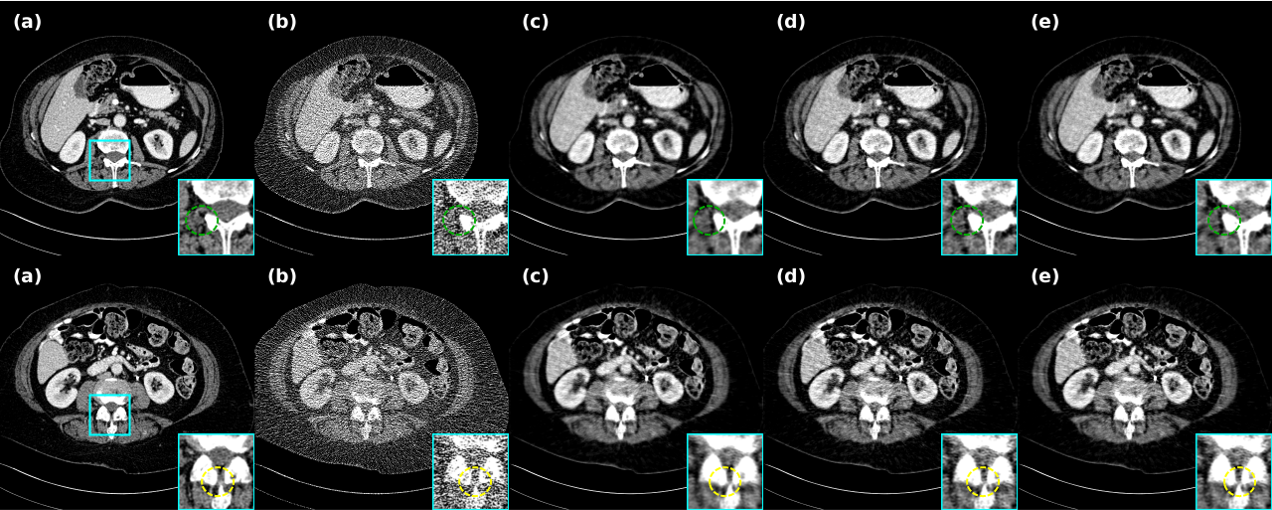

4.6.1 Validity of the dual domain

In this study, we first analyze the model from the overall perspective, and for the process of denoising the LDCT projection domain first, followed by optimization of the image domain, we conducted ablation experiments for the single stage and the overall stage, respectively. As shown in Fig. 10 and Table 3, the single-stage log projection domain denoising reveals that there is insufficient denoising for the noise, incomplete denoising of local muscle tissues, and some details of the skeleton are not fully recovered, and after the knowledge distillation in the image domain, the information is well recovered. This also shows that the initial reconstruction and the original information both act as the guiding information for the reconstruction to check and fill in the gaps.

4.6.2 Importance of adaptive enhancement of data similarity in log projection domain

After analyzing the effectiveness of the dual-domain phase, we focus on the proposed adaptive weighting strategy for data similarity in the projection domain phase. This strategy is proposed to shorten the dissimilarity between contextual sub-data to fit the theorem of the method part. So it focuses on highlighting the loss weight of similarity and ignoring the excessive part of dissimilarity. Fig. 11 and Table 3 show that the feature information of the image recovered after this strategy is well-defined, whereas not taking this strategy presents the effect of feature smoothing and gradient disappearance. This can lead to the subsequent refinement stage of the image domain not being able to discriminate well between the noise information and the organizational structure, and falling into a sub-optimal situation.

4.6.3 Pixel-level self-correcting validity and difference from fixed weights

The above ablation analysis for the training phase can be sufficiently justified by our approach. Subsequently, we carried out the difference between self-correction at the pixel level of the inference process and taking fixed weights. Fig. 12 and Table 4 add fully illustrate the situation, with fixed weights we selected as , and even selected as , even though this is not in line with the original intent of the dual-stage. As can be seen, our pixel-level fusion can make a balance between and for each pixel, laying the groundwork for entering into image inference, and showing competitive results in both metrics and reconstruction.